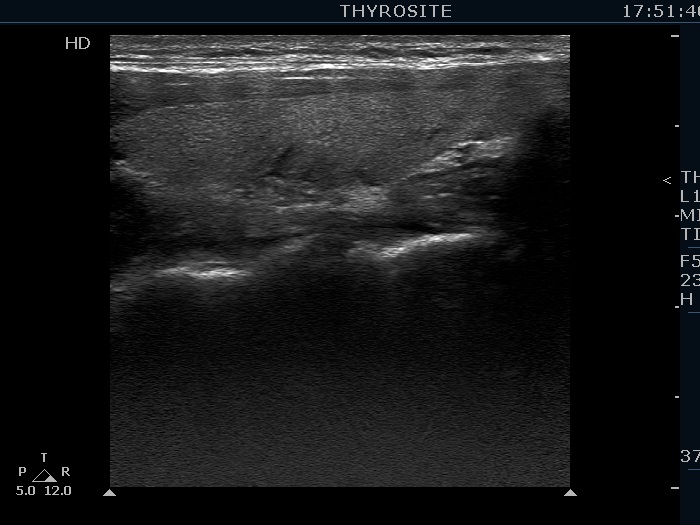

Intranodular hyperechogenic figures - case 1730 (ultrasonographic picture 5)

Left lobe, longitudinal view.